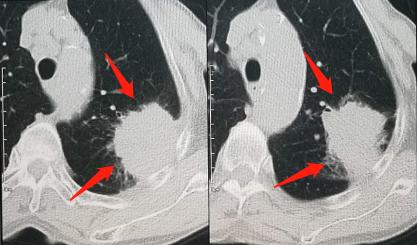

第三例肺癌病人,是一位78岁的老太太,抽烟60年,嗯,从18岁就开始吸烟了,有多年的支气管炎和肺气肿(慢阻肺),胸部CT发现左上肺大肿块:

我们知道,慢阻肺是肺癌的高危人群之一,并且在正常肺与间质病变的边缘常高发肿瘤,以肺鳞癌最常见,其次是小细胞肺癌。

这是一例肺鳞癌。

在慢阻肺基础上发生的肺癌,常常预后不良,原因之一是患者的肺功能受多年吸烟的影响,已经下降好多。

而肺鳞癌大多对放疗敏感,这位老太太的病灶位于肺外围,方便放疗定位治疗,可以借以延长寿命。